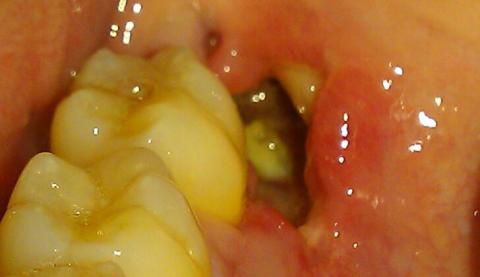

Days later, Leo was in excruciating pain. A foul smell filled his mouth, and even cold air felt like a knife in the jaw. The empty socket was a dry, painful crater. The new dentist had not only pulled the wrong tooth but had also failed to protect the correct socket, leading to a severe case of Alveolar Osteitis—Dry Socket.

A dry socket occurs when the blood clot that forms after an extraction is dislodged or dissolves, exposing the underlying bone and nerves.